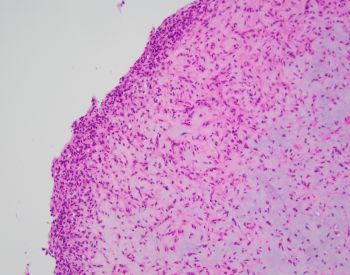

81-year-old female with a remote history of follicular lymphoma was undergoing evaluation for possible disease recurrence when an incidental right breast mass was identified.